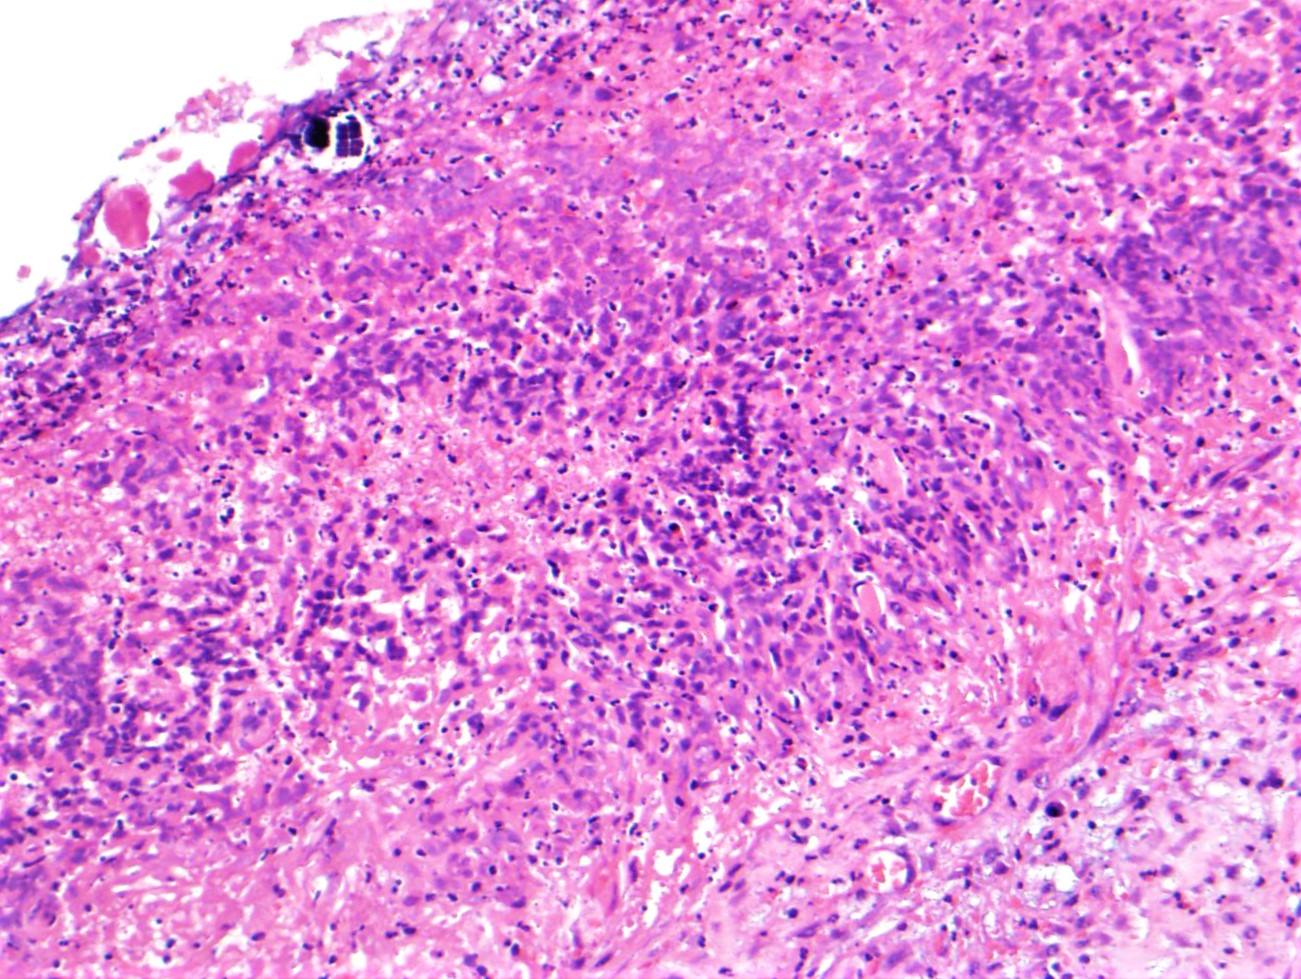

The entire ulcer was submitted for microscopic examination. No malignancy or H. Pylori identified. However, multiple bacterial cocci were noted at the ulcer bed. They are basophilic-stained and cuboid-shaped bacteria that arranged in tetrad packets, consistent with Sarcina ventriculi.

Sarcina ventriculi is anaerobic gram-positive coccus that grows in an acidic environment. It is typically diagnosed with a hematoxylin-eosin stain and, if needed, with a Gram special stain. It was first described by Goodsir in 1842 as a human pathogen. The pathogenic status of Sarcina in human is still unclear. However, association of Sarcina with a patient with gastric perforation, emphysematous gastritis, and peritonitis as well as occurring in the background of gastric adenocarcinomas has been reported. It can normally be found in the soil and air, where it can survive for years by forming spores at alkaline pH. It ferments Carbohydrate as an energy source. Sarcina species, whose natural habitat is the soil, is probably ingested with soil particles present in the food. Various reports in veterinary literature have implicated the Sarcina species in the development of gastric dilatation and death in livestock, cats and horses.

Differential diagnoses for S ventriculi are Sarcina maxima and Staphylococcus species. The most helpful feature in light microscopy to differentiate S ventriculi from S maxima is the thick extracellular layer present on the outer surface.